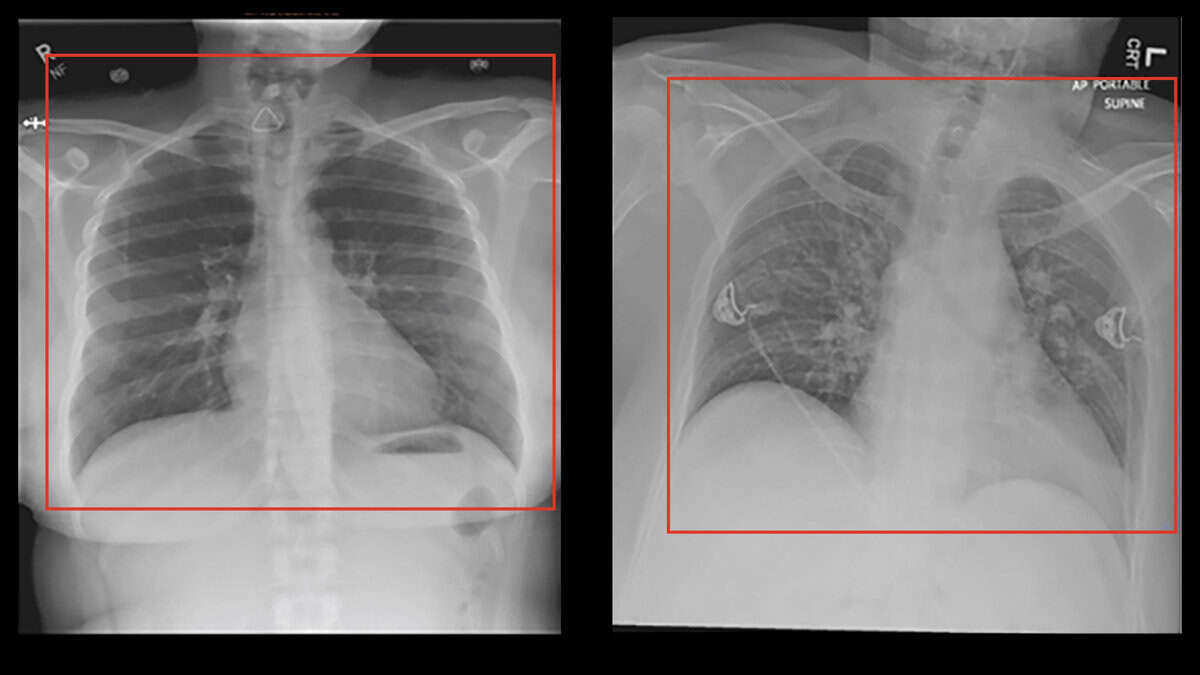

Back in May 2020, with Covid-19 everywhere on the rise and scarce resources to diagnose it, there was tremendous pressure for quick diagnostic or screening tests, which AI applications were hastily developed to satisfy. Several Machine Learning algorithms were trained to recognise signs of covid in chest radiographs and CT scans, scoring high in internal metrics of performance. On the basis of these, some advocated the fast implementation of mass scale CT-scans to air travelers as a quick and efficient screening. Luckily the dystopian travel process described in the image was never implemented. Only later was it actually shown that none of these algorithms was any good, despite promising internal precision. A paper in Nature Machine Intelligence (Roberts et al 2021) concluded that not one of the 62 models reviewed was any good in actual clinical application, with most of the flaws being identified in the process that was used to train the algorithms, which was plagued by deficiencies and bias. In one case for example the positive covid patients used to train the model were all bedridden, while the healthy controls were standing. The algorithm showed high internal precision in detecting Covid-19 on the basis of chest radiographs, but failed to perform in actual clinical setup. It was then realised that the algorithm had learned to identify if the patient was in lying or standing position, rather than the Covid-19 status.

Spot the ...x differences..!

Bedridden patients were frequently x-rayed with portable devices and under different settings. The patients' position was not as symmetrical as the standing patients, with slight rotations and irregular placement in the frame. The radiographs were also sometimes marked with text indicating portable device and subpine position. In a very cool demonstration of street-smart intelligence, the machine learned how to pass the exam, but never really learned the content...! This can be a typical case of what we call "overfit" algorithms, where the machine learning has evaluated too specific patterns in the training sample, including irrelevant ones and noise, thus becomes increasingly unable to detect relevant patterns in new samples, although highly successful in the training samples.